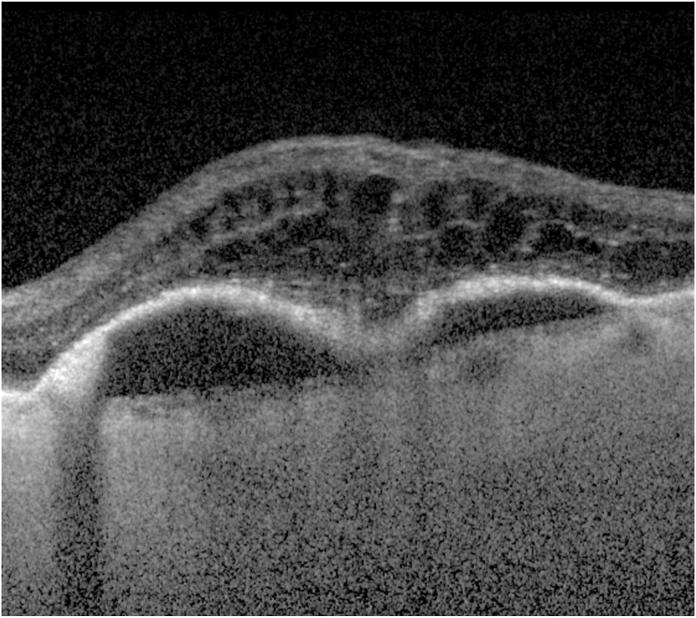

This prospective case series investigates the visual and anatomical outcomes including detailed volumetrics of eyes with vascularized pigment epithelial detachments (PED) treated with aflibercept in eyes with neovascular age-related macular degeneration (nAMD) through meticulous analysis in a reading center setting.

We conducted a single-arm multicenter, prospective, open-labeled, interventional case series, comparing visual and anatomic outcomes at 12 months with baseline for intense aflibercept therapy. Eyes with submacular vascularized PED due to AMD received 2.0 mG of intravitreal aflibercept at baseline and then monthly for 6 months. During the subsequent 6 months, mandatory aflibercept therapy was given for every other month, while additional aflibercept injections were allowed between mandatory injections if necessary, at 4 weeks after last injection, contingent on pre-defined visual and anatomic re-treatment criteria. Standardized ETDRS vision measurement, anterior and posterior segment examination, and high-density spectral-domain optical coherence tomography scans were obtained at baseline and monthly, while fundus photography and fluorescein angiography were obtained at baseline, 3,6, and 12 months. Indocyanine-green angiography was obtained at baseline and 3 months. Meticulous multidimensional assessment of the scanned multimodal serial images was then performed by Doheny Image Reading Center.

Of 36 eyes and patients with mean age of 80, mean baseline and 12-month-ETDRS BCVA was 59 ± 8.9 letters (20/66), and 65 ± 27 letters (20/50), respectively; (6.5 letters improvement, p = 0.02). Significant reductions from baseline to month-12 were noted for multiple anatomic measures, including PED maximum height, entire lesion and central 1-mm subfield of PED mean thickness and volume, and mean subretinal hyperreflective material (SHRM) thickness and volume, also entire lesion of retinal thickness, retinal volume, and mean subretinal fluid (SRF) thickness (mean reductions in magnitude ranging from 37.5 to 91.7%, all p < 0.001). FA measurements also showed significant decrease from baseline to month-12, including area and greatest linear diameter (GLD) of fibrovascular PED, area and GLD of NV area and leakage (mean reductions in magnitude from 41.9 to 87.7%, p value from 0.002 to <0.001). This case series shows that while majority of reductions in SRF volume occurred during first month from baseline, majority of reduction in retinal, PED, and SHRM volumes occurred during first 2 months after onset of anti-VEGF injections. RPE tears developed in 5 eyes (13.9%) correlating with eyes with large PED height and volume at baseline (mean height >800 μm, mean volume >4 mm). Geographic atrophy (GA) was noted in only 1 eye at baseline, but in 16 eyes (44.4%) by 12 months.